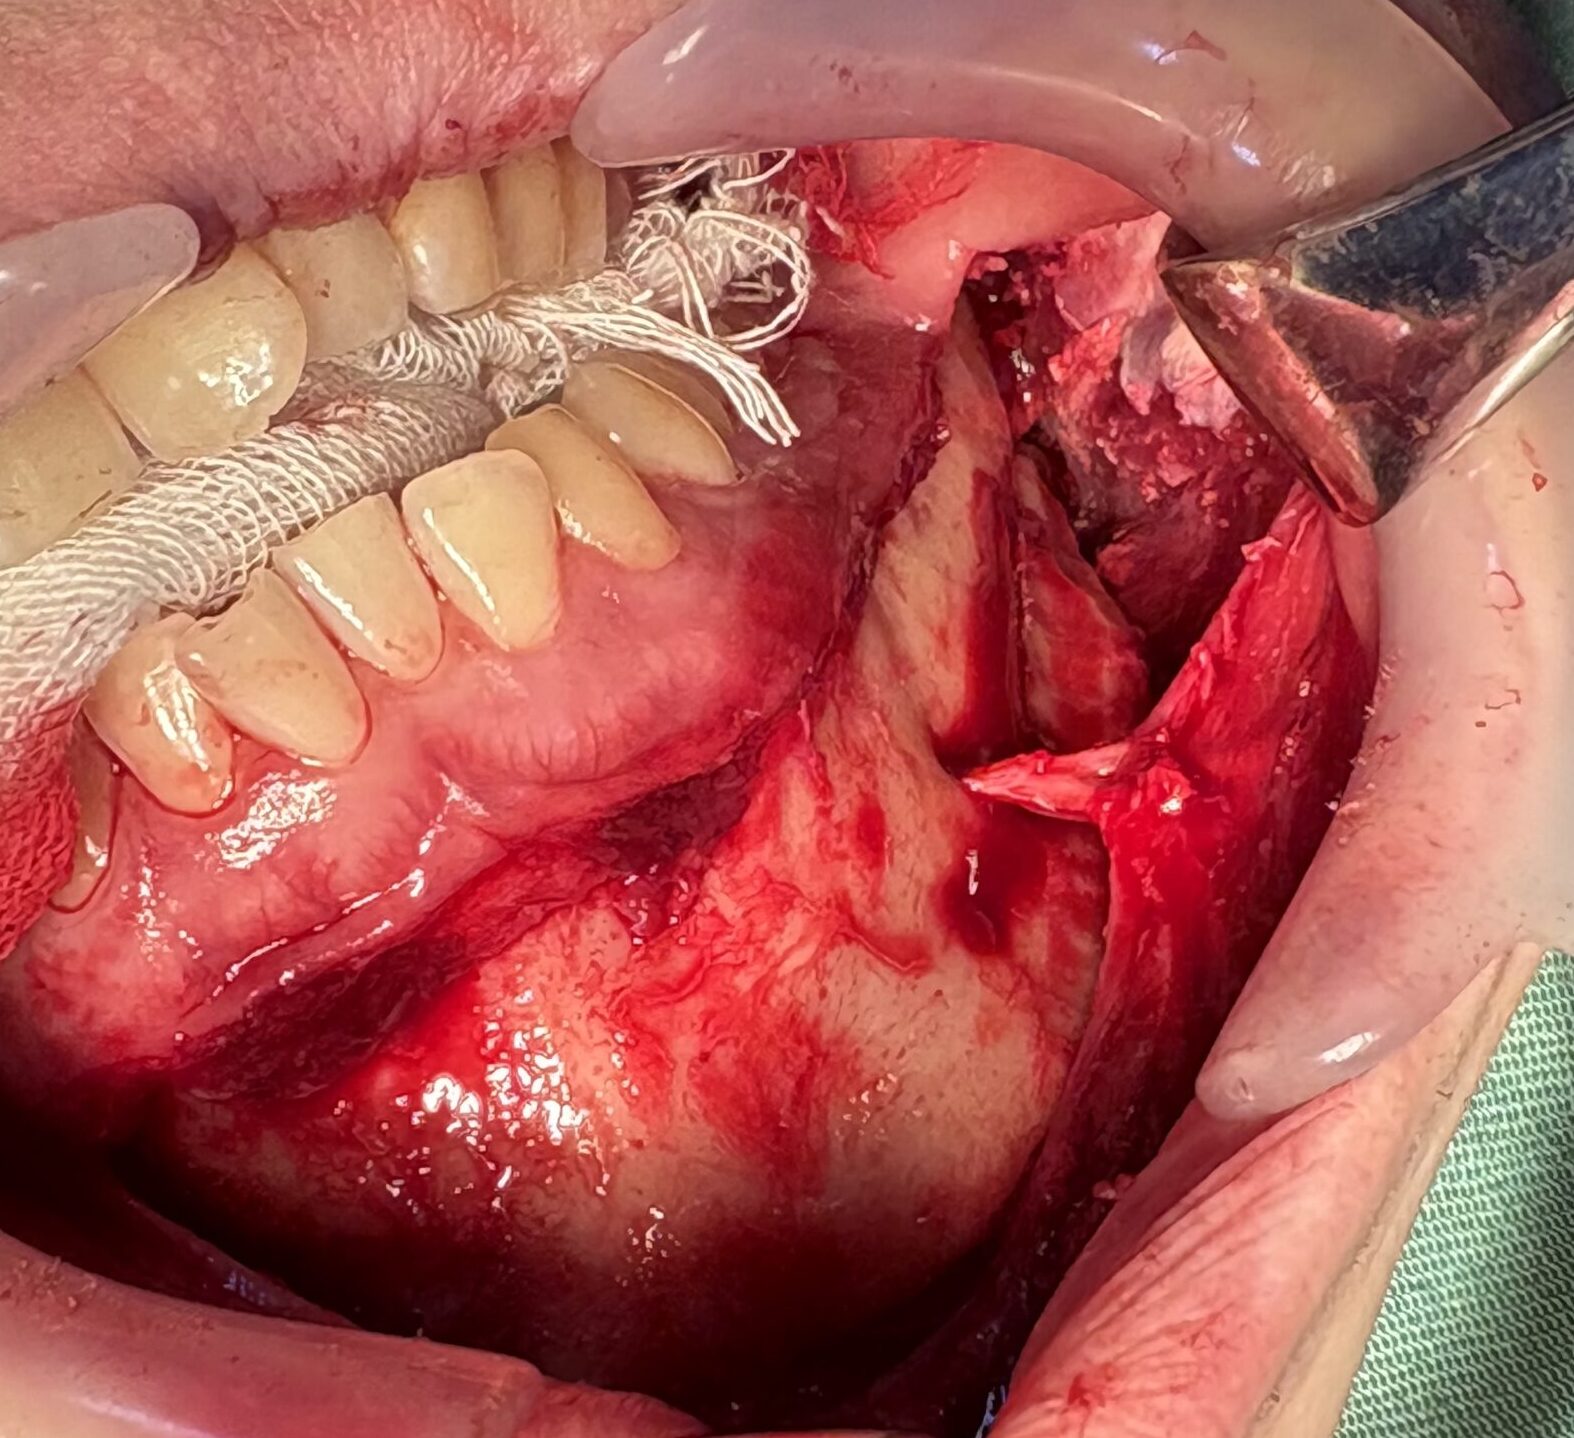

切開線から下顎のエラの部分まで筋肉や脂肪をキレイに剥がします。

この画像では筋肉の一部(咬筋)の筋層がキレイに見えています。

V-Line形成ではおとがい孔をまたいで骨を切除してくるので、オトガイ神経をよく伸ばして切れないように神経繊維をバラバラにほぐします。

この画像ではエラの部分からオトガイ孔の直下までコツ切り線が伸びています。このまま前まで一気に切り落とします。